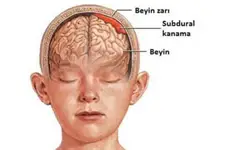

Beyin Dokusunun Sağlık Üzerindeki Etkileri Beyin dokusunun sağlıklı bir şekilde işlev görmesi, genel sağlık üzerinde büyük etkiye sahiptir. Beyin dokusundaki hasar veya bozulmalar, birçok nörolojik hastalığın temelini oluşturur. Öne çıkan sağlık sorunları arasında: